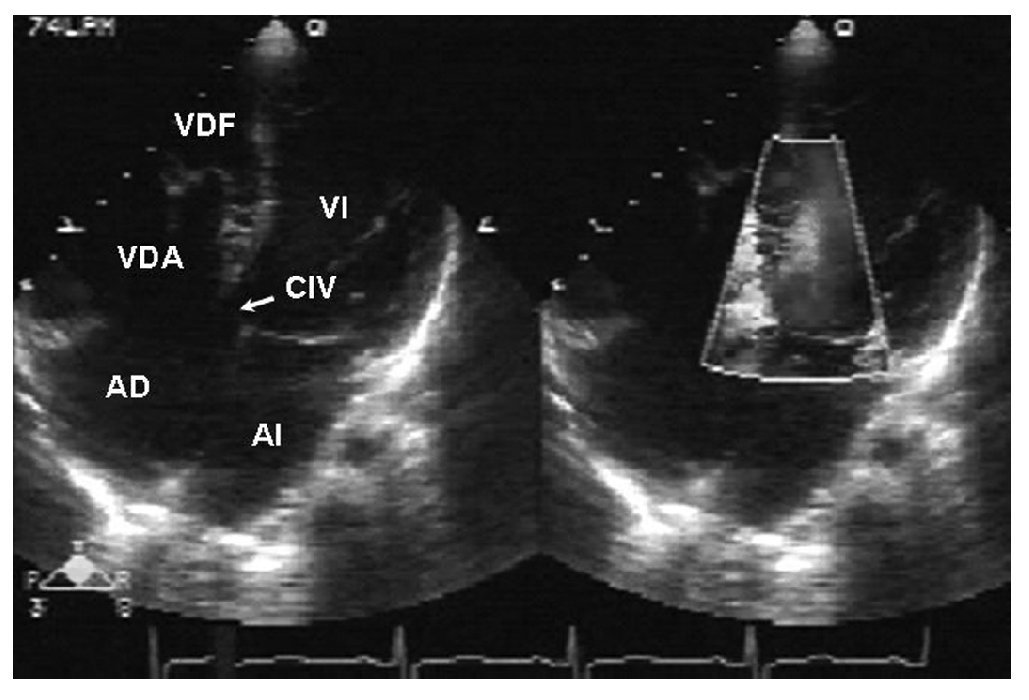

El electrocardiograma evidenció un crecimiento de las cavidades derechas. La radiografía de tórax demostró cardiomegalia en grado II a expensas de las cavidades derechas, el abombamiento del cono de la pulmonar, con aumento de la trama vascular pulmonar (fig. 1). Se realizó un ecocardiograma que evidenció una anomalía de Ebstein con adosamiento del 50 %, insuficiencia tricuspídea moderada, con datos de hipertensión arterial pulmonar y CIV muscular alta de 14 mm de diámetro (figs. 2 y 3). La función ventricular izquierda estaba conservada y presentaba dilatación del tronco y las ramas de la arteria pulmonar. Se realizó un cateterismo cardíaco con el fin de precisar las resistencias vasculares pulmonares. Se observaron una presión sistólica de la arteria pulmonar de 92 mmHg (media de 40 mmHg); un índice de resistencia pulmonar total de 12,7 U Wood, que con la administración de oxígeno disminuyó a 2,46 U Wood; presión sistólica aórtica de 95 mmHg (media de 60 mmHg); angiografía pulmonar magnificada con una mancha capilar heterogénea; arterias monopediales presentes y buen vaciamiento del medio de contraste (figs. 4 y 5). Se sometió a la paciente a tratamiento quirúrgico, con un tiempo de circulación extracorpórea de 111 min y de pinzamiento aórtico de 86 min. Se realizaron una plastia tricuspídea, la plicatura de la "porción auriculizada" del ventrículo derecho, el cierre directo de foramen oval y el cierre de la CIV con parche de pericardio bovino valvulado con fenestración de 6 mm. La estancia en la terapia posquirúrgica fue de 48 h; se la extubó en las primeras horas del postoperatorio, con apoyo inotrópico con milrinona y dobutamina. A las 72 h de la cirugía la paciente presentó una crisis convulsiva que se trató con diazepam. Se le realizaron una resonancia magnética de cráneo que no evidenció alteraciones y un ecocardiograma de control que mostró insuficiencia tricuspídea severa. Evolucionó con importante compromiso hemodinámico y requirió de mayor soporte inotrópico. Presentó varios episodios de arritmias, como taquicardia supraventricular y taquicardia ventricular y, finalmente, falleció a los 5 días posteriores a la cirugía.

Figura 3 Ecocardiograma en vista apical de cuatro cámaras. Se observa un adosamiento de la valva septal de la tricúspide y comunicación interventricular; con el Doppler color se evidencia el paso de flujo a través de la comunicación interventricular. AD: aurícula derecha; AI: aurícula izquierda; CIV: comunicación interventricular; VI: ventrículo derecho.